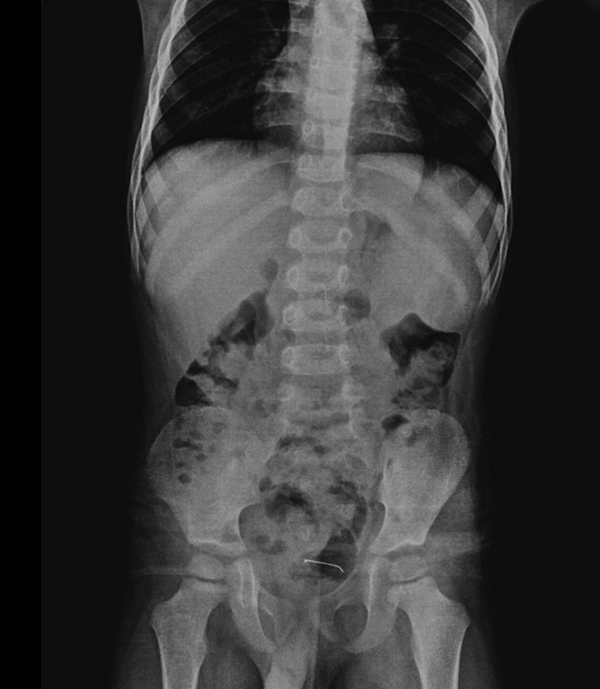

Karın ağrısı şikayeti bulunan çocuğun çekilen röntgeninde, mesane duvarında metal cisim olduğu tespit edildi. Uzun süre vücutta kalan 3 santimetre civarındaki toplu iğnenin, mesane duvarına yapıştığı belirlendi.

Hastanın kontrollerinde, yuttuğu cismin doğal yollarla vücuttan çıkmadığını tespit ettiklerini anlatan Kamçı, "Bunun üzerine ameliyat kararı aldık. Ameliyatta cismin mesane duvarına yapıştığını gördük. Cerrahi operasyonla 3 santimetre civarındaki toplu iğneyi çıkardık. Hastayı birkaç gün takipte tuttuk. Genel sağlık durumu iyi olan hastamızı taburcu ettik." diye konuştu.